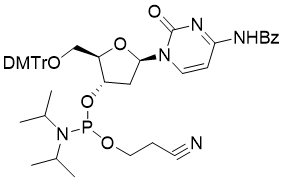

馬鞍山致研生物醫(yī)藥科技有限公司成立于馬鞍山市鄭浦港新區(qū)現(xiàn)代產(chǎn)業(yè)園。公司專(zhuān)注于生物小分子、醫(yī)藥中間體相關(guān)產(chǎn)品的研發(fā)和生產(chǎn),產(chǎn)品主要包括DNA亞磷酰胺單體、RNA亞磷酰胺單體、特殊單體以及按照客戶(hù)要求定制的RNA和DNA,并且公司提供定制合成等方面的研究服...

馬鞍山致研生物醫(yī)藥科技有限公司成立于馬鞍山市鄭浦港新區(qū)現(xiàn)代產(chǎn)業(yè)園。公司專(zhuān)注于生物小分子、醫(yī)藥中間體相關(guān)產(chǎn)品的研發(fā)和生產(chǎn),產(chǎn)品主要包括DNA亞磷酰胺單體、RNA亞磷酰胺單體、特殊單體以及按照客戶(hù)要求定制的RNA和DNA,并且公司提供定制合成等方面的研究服...